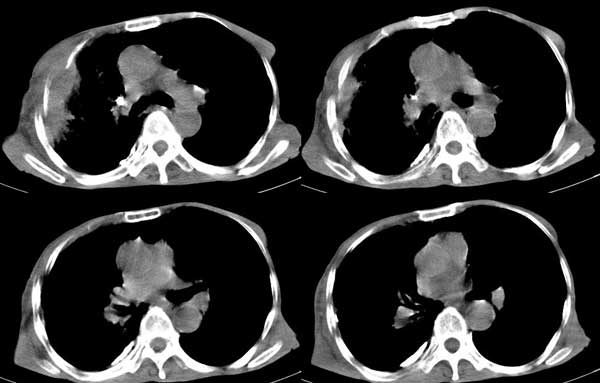

患者男,81岁,咳喘10余年,继往结核病史,发现胸部体表肿物(具体时间不详)就诊

右侧胸廓塌陷。右前上外侧胸壁软组织肿块,其内见有低密度影,肋骨呈溶骨性表现。右肺上叶见大量的间质纤维化表现。右侧膈肌上抬。

患者男,81岁,咳喘10余年,继往结核病史,发现胸部体表肿物

考虑:1、继发性结核,右结核性胸膜炎伴胸壁结核性感染

2、右侧胸壁恶性肿瘤。

肺尖巨大肿块影阴,胸壁受侵肋骨破坏,肿块密度不均且穿破胸壁入皮下,应该是:肺上沟癌;由于肺内有斑片状播散病灶,因此不排除胸壁结核。

患者男,81岁,咳喘10余年,继往结核病史,发现胸部体表肿物。

考虑:1 右侧胸壁恶性肿瘤(多考虑:胸膜间皮瘤)。

2 继发性结核,右结核性胸膜炎伴胸壁结核性感染。